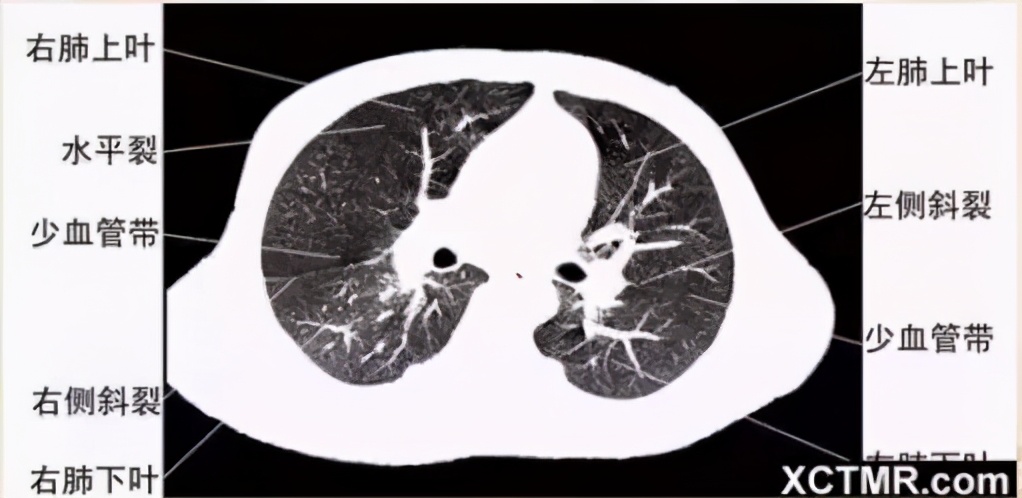

肺窗